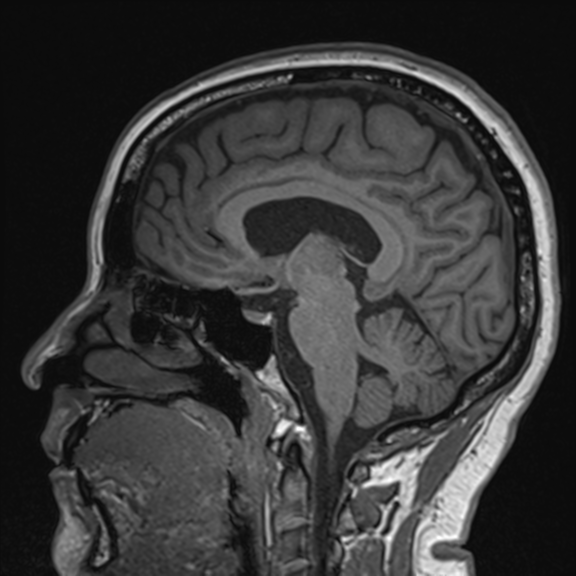

This imaging technique provides a non-invasive look inside the brain using powerful magnetic resonance technology. It is particularly beneficial for individuals with stroke risk factors.